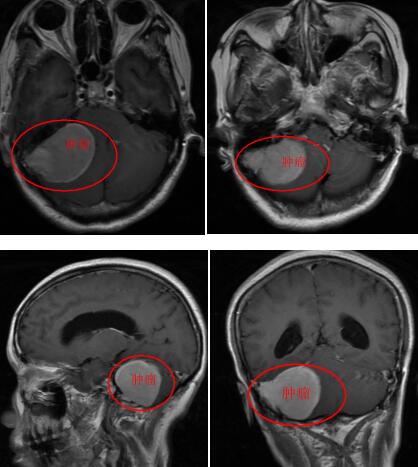

在完善相关检查后,初步考虑为右侧桥小脑角占位,良性脑膜瘤可能性比较大。杨阿姨及其家人被告知得了脑瘤后,决定听从医生的建议进行手术切除。

据悉,杨阿姨颅内的肿瘤位于岩斜区,这个区域的肿瘤位置比较深,位居颅底近中央区,毗邻脑干、重要血管与颅脑神经等重要部位,手术十分困难。因此,岩斜区脑膜瘤切除手术,是神经外科领域极具挑战性的手术。

在完善术前准备并对手术方案进行认真论证后,神经外十科医疗团队采取右侧颞下联合乙状窦后入路的方式,行右侧幕下岩斜区脑膜瘤切除术。手术的难点在于肿瘤显露困难,它位于脑子底部正中间,起源于双侧三叉神经内侧、面神经内侧、上中斜坡上缘、上斜坡下缘到中斜坡的下缘,稍有差池便会损伤颅神经、脑血管。术中,在显微镜下,医生凭借精湛的手术技巧和丰富的临床经验对肿瘤进行精细剥离,肿瘤全切。